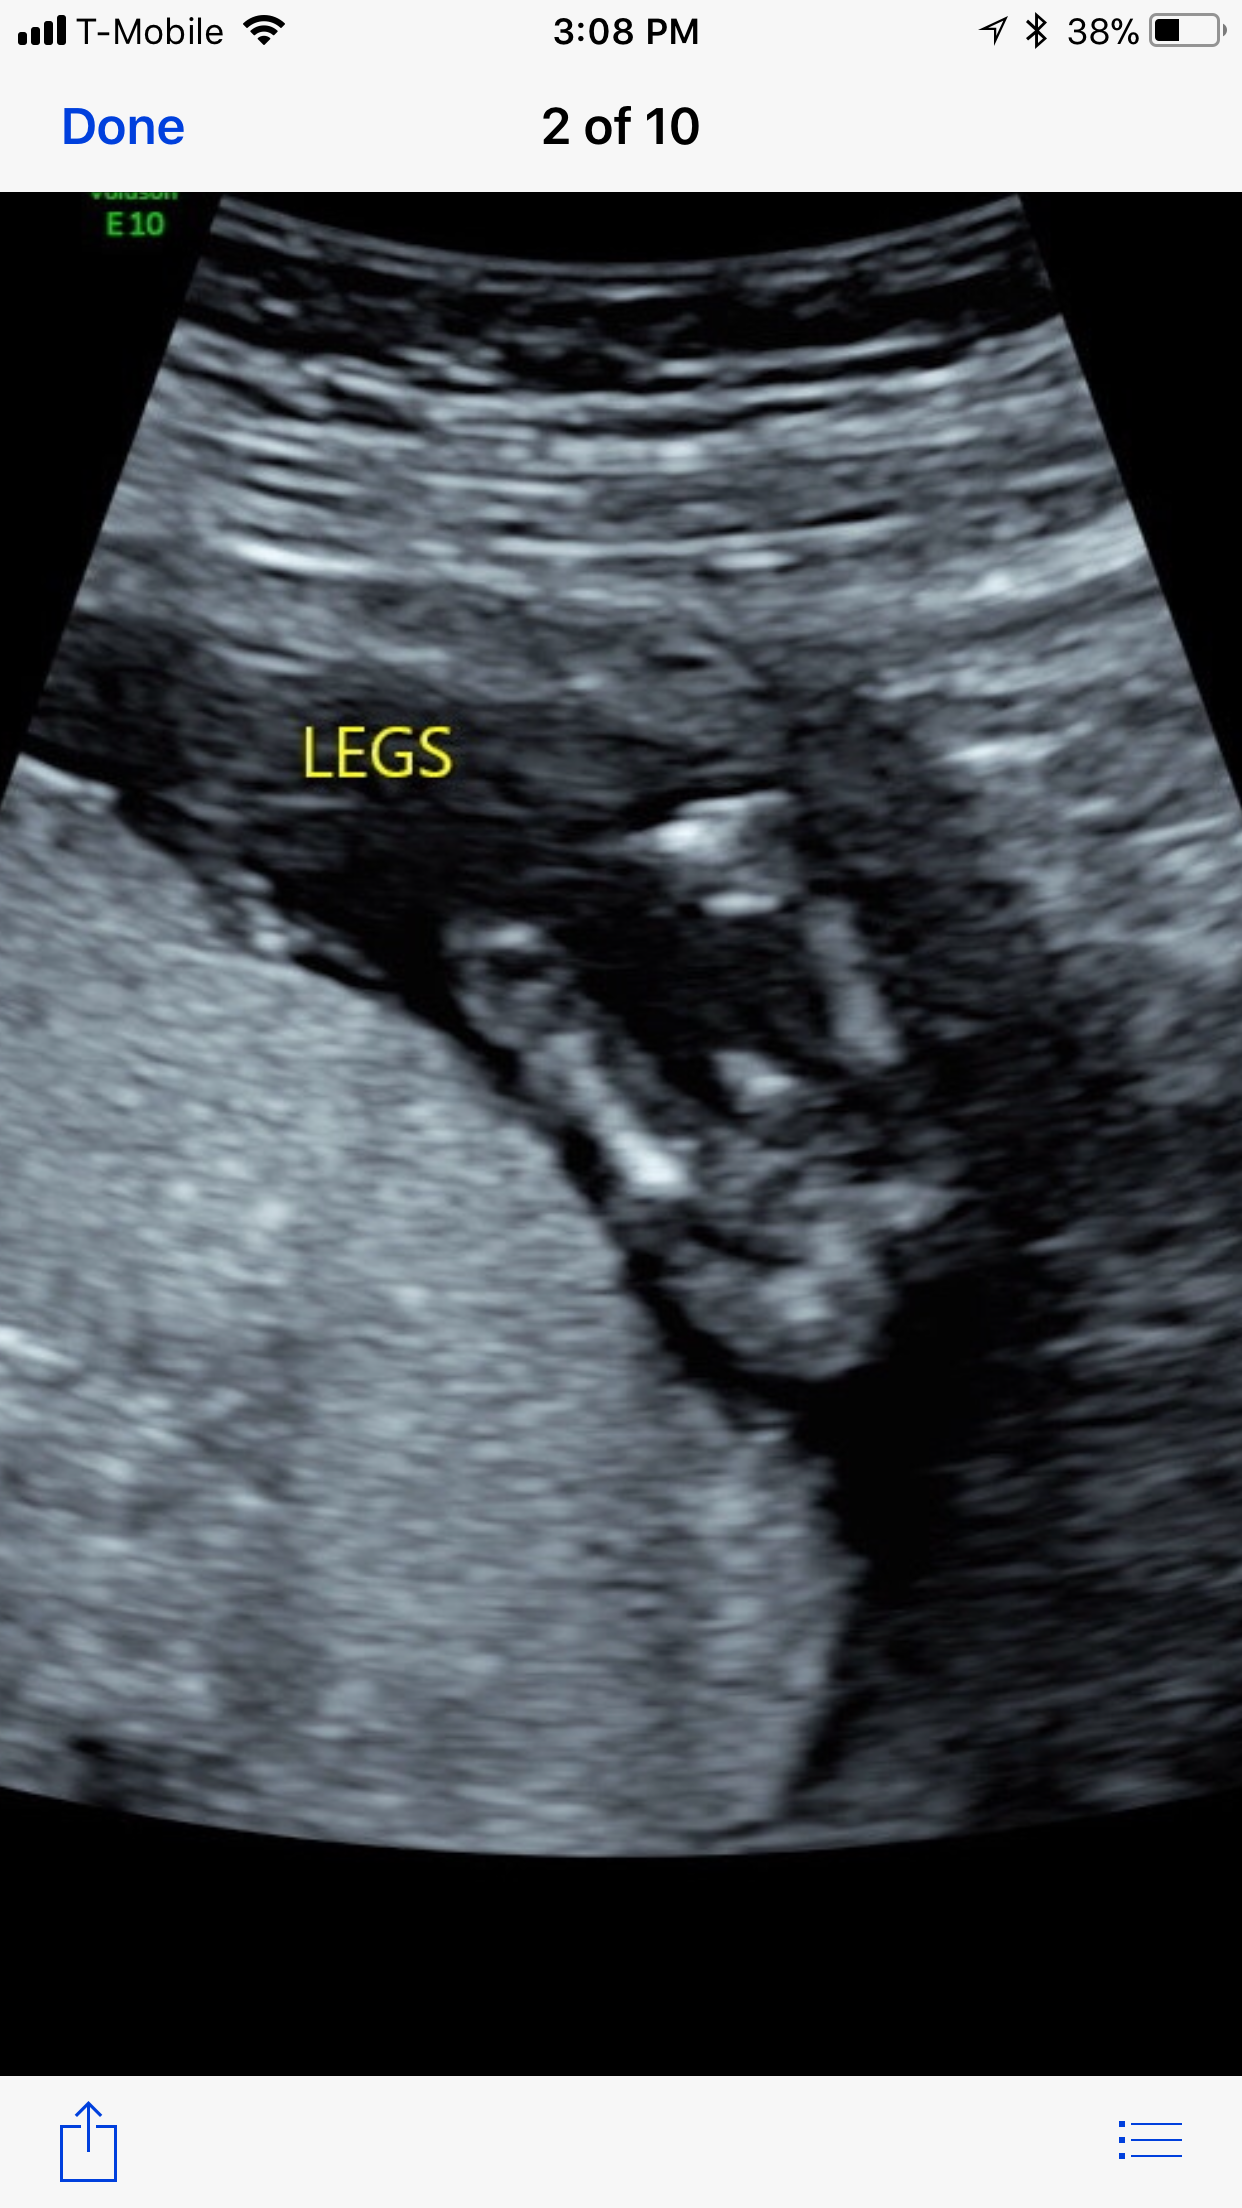

Umbilical cord or boy parts?

Why is this posted on several boards?

Sorry OP we can't tell you ask the tech